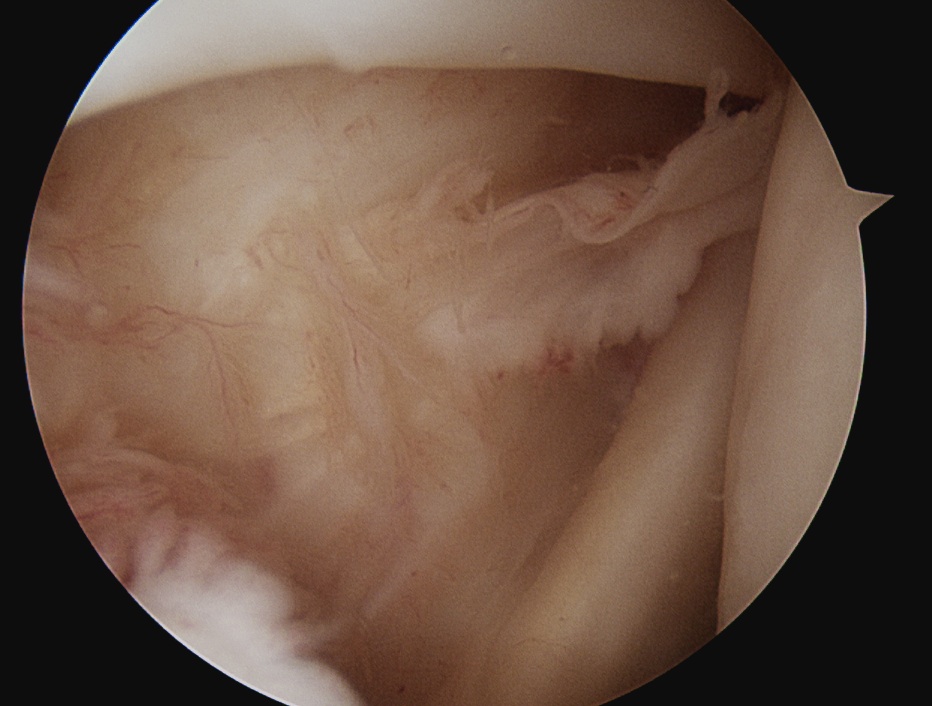

Rotator Interval - triangle of glenoid medial, biceps superior, subscapularis inferior

Humeral head cartilage

Glenoid cartilage

Labrum - anterior / inferior / posterior

Biceps tendon / insertion

Subscapularis

Glenohumeral ligaments

Undersurface supraspinatus - abduct arm

Infraspinatus / bare area / Hill Sachs